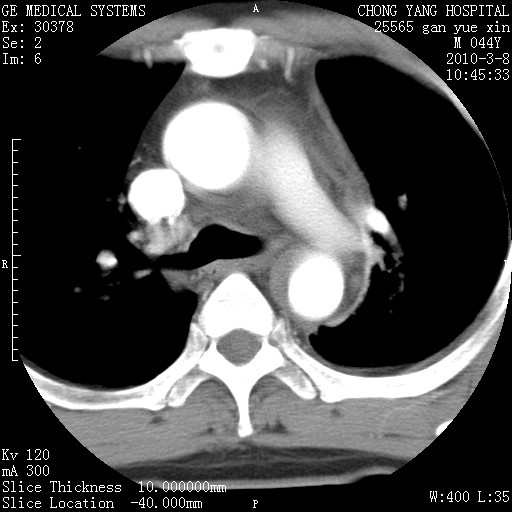

标题: CT24940:主动脉增强,典型病例。 [打印本页]

标题: CT24940:主动脉增强,典型病例。

夹层动脉瘤。

动脉夹层

夹层动脉瘤,典型

主动脉夹层。

动脉夹层的分型:

⒈debakey分型:根据主动脉夹层累及部位,分为三型:ⅰ型:原发破口位于升主动脉或主动脉弓部,夹层累及升主动脉、主动脉弓部、胸主动脉、腹主动脉大部或全部,少数可累及髂动脉。ⅱ型:原发破口位于升主动脉,夹层累及升主动脉,少数可累及部分主动脉弓。ⅲ型:原发破口位于左锁骨下动脉开口远端,根据夹层累及范围又分为ⅲa,ⅲb。ⅲa型:夹层累及胸主动脉。ⅲb型:夹层累及升主动脉、腹主动脉大部或全部。少数可累及髂动脉。

⒉stanford分型:a型:夹层累及升主动脉,无论远端范围如何。b型:夹层累及左锁骨下动脉开口以远的降主动脉。

夹层动脉瘤,少量胸水

夹层动脉瘤;左侧少量胸腔积液。

典型主动脉夹层。